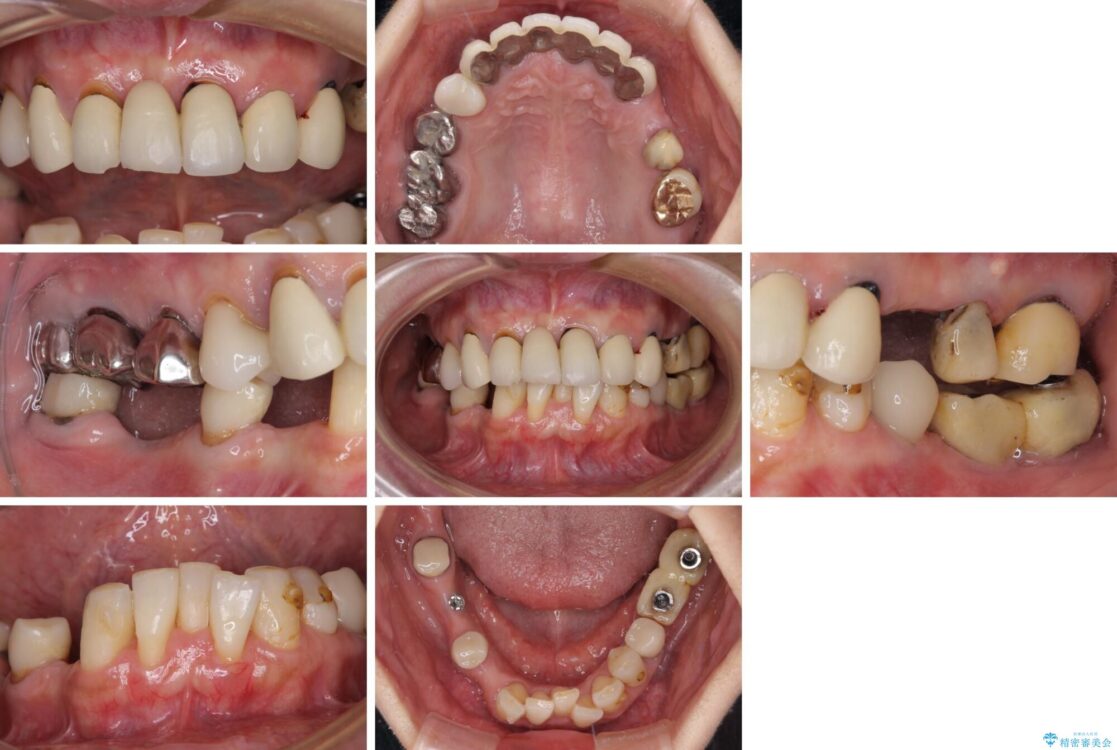

ご主人が当院に通院されていたことで、ご紹介により来院されました。 以前通院していた医院で、奥歯のインプラント埋入、前歯部のインビザライン矯正を行ったものの、そのまま放置してしまったとのことで来院された患者様です。

治療計画

下顎前歯や上顎奥歯などをワイヤー装置により部分矯正を行い、歯列を整えた上でインプラント部分を含めてオールセラミッククラウンにて補綴治療を行うこととしました。

治療後について

インプラント上の仮歯がボロボロになり、前歯に非常に負担のかかる状態であったため、早急に奥歯の仮歯を修復し、矯正治療、奥歯の補綴治療、前歯の補綴治療と順々に進めて行きました。

治療前

• 放置したインプラントとインビザライン 全顎リカバリー治療 治療前画像

治療途中